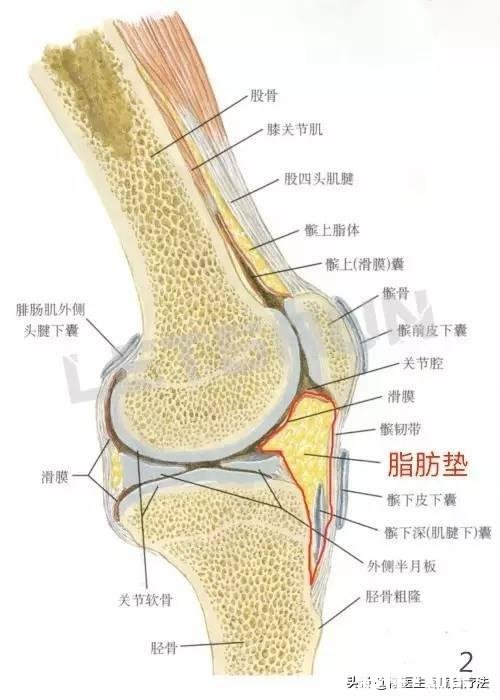

膑下脂肪垫损伤膝关节的膑下脂肪垫位于髌骨前方膑腱的里面,它的功能是润滑缓冲关节 。长期的下山、走路就会过度挤压膑下脂肪垫,出现无菌性炎症导致疼痛,疼痛会传导到足跟底部 。

文章插图